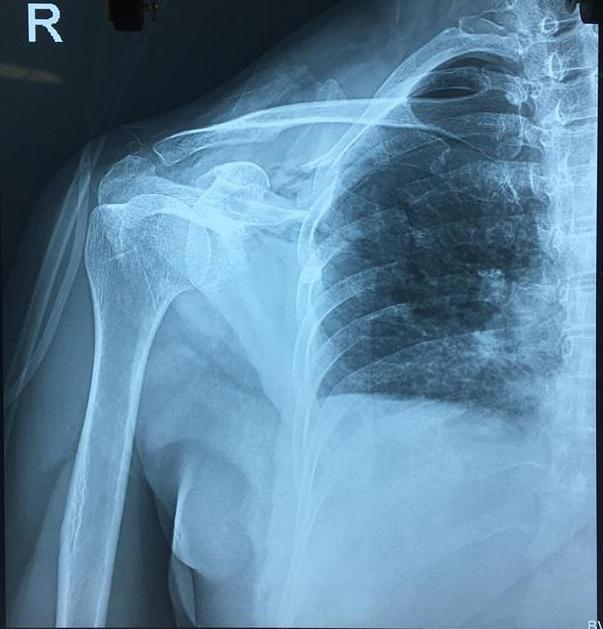

Hình chụp X-Quang tổn thương của bệnh nhân N.

Cụ thể, bệnh nhân có vết thương thấu ngực, do dao đâm từ bả vai xuyên từ sau ra trước gây tổn thương rách da 10 cm, gãy xương vai, đứt lìa ba xương sườn 4, 5, 6 gây tràn máu, tràn khí màng phổi.